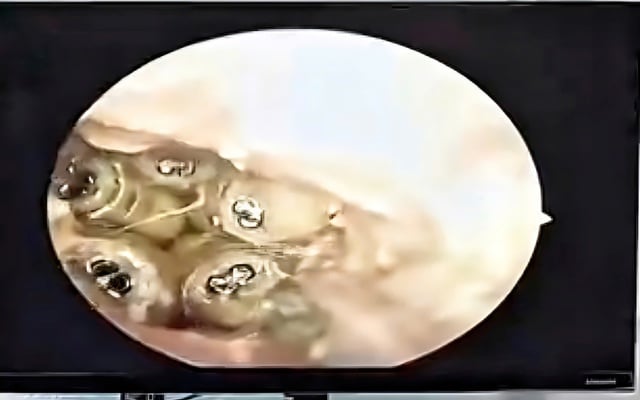

แมลงวัน 5 ตัวอาศัยอยู่ในหูของผู้ป่วย

ภาพ: ตัดจากคลิป

หลังจากทำความสะอาดของเหลวในช่องหูแล้ว แพทย์ได้นำหนอนแมลงวัน 5 ตัวที่ยังมีชีวิตและแมลงที่ตายแล้ว 1 ตัวที่ติดอยู่กับแก้วหูออก แพทย์ระบุว่า เนื่องจากผู้ป่วยไม่สามารถดูแลตัวเองได้ ขณะทำกิจกรรมประจำวัน แมลงเหล่านี้อาจคลานเข้าไปในหู ทำรัง และวางไข่ ซึ่งต่อมาก็ฟักออกมาเป็นหนอนแมลงวัน